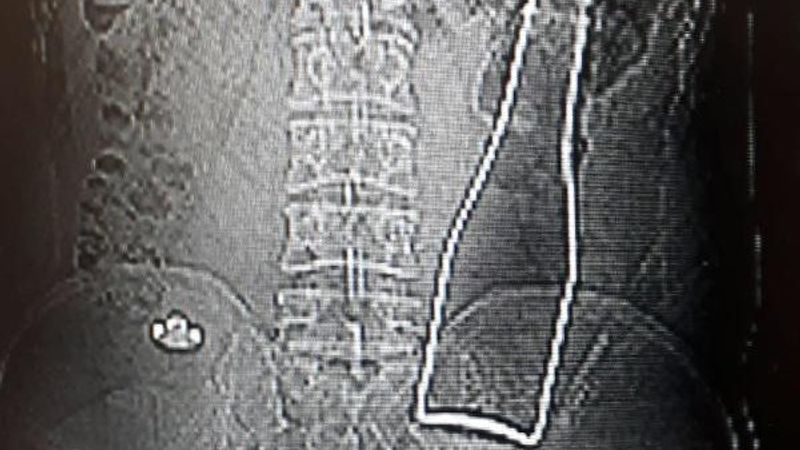

Karaman'da karın ağrısı şikayetiyle hastaneye giden Afganistan uyruklu A.E. adlı erkeğin çekilen röntgen filminde, kalın bağırsağında şişe olduğu ortaya çıktı.

Çekilen röntgen filminde, A.E.'nin kalın bağırsağının bulunduğu bölgede şişe olduğu tespit edildi.